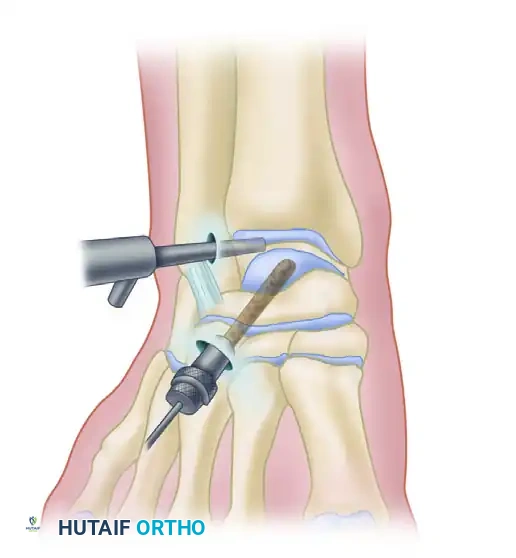

Arthroscopic retrograde drilling and bone grafting as described by Stone and Gould. (A) A guide pin is placed through the sinus tarsi using a modified ligament guide. (B) Graft material is compressed into the channel.

Surgical Steps:

1. Targeting: Under arthroscopic visualization, the intact articular cartilage is confirmed. A modified anterior cruciate ligament (ACL) drill guide is placed through the anterolateral portal, targeting the center of the lesion.

2. Drilling: A guide pin is advanced percutaneously from the sinus tarsi (for medial lesions) or the medial talar neck (for lateral lesions) into the subchondral cyst, stopping just short of the articular cartilage.

3. Fluoroscopic Confirmation: Intraoperative C-arm fluoroscopy confirms the trajectory and depth.

4. Decompression and Grafting: The tract is over-drilled. The cystic contents are curetted. To prevent articular collapse, the void is backfilled. Options include cancellous autograft, surgical-grade calcium sulfate, or bone marrow aspirate concentrate (BMAC) harvested from the iliac crest.